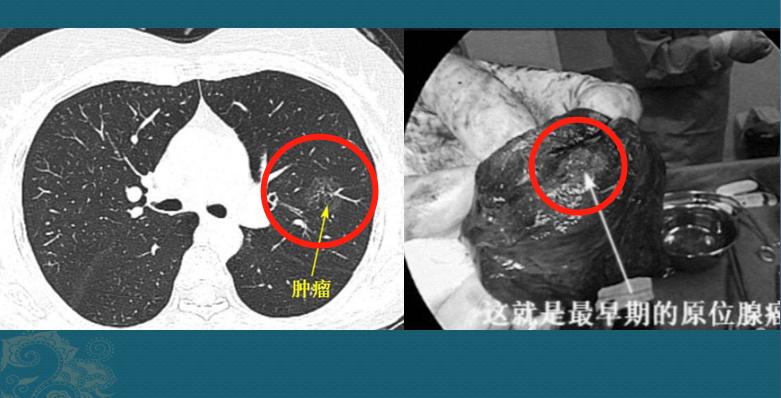

病例2,磨玻璃结节2.6cm,原位腺癌

这是一位50多岁的女士,体检发现左肺磨玻璃结节,2.6cm手术病理原位腺癌:

朋友们没看错,2.6cm,原位癌,≤3cm,癌细胞完全贴壁生长,无间质、血管和胸膜浸润;如果肿瘤被完整切除,5年生存率为100%。

当然了,有时候即使在显微镜下仔细观察病理,也难以区分某些原位癌(AIS)和微浸润癌(MIA),但治疗效果是一样的。

有个知识点要注意,纯磨玻璃结节如果>3.0cm,不属于微浸润,要归类于浸润性腺癌,分期为T1a。如下图:

本图片来自山东肿瘤医院黄勇教授

这是一位49岁男子,体检发现右肺纯磨玻璃结节,边界清晰,形态不规则,最大径3.9cm,浸润性腺癌,影像分期属于T1a。